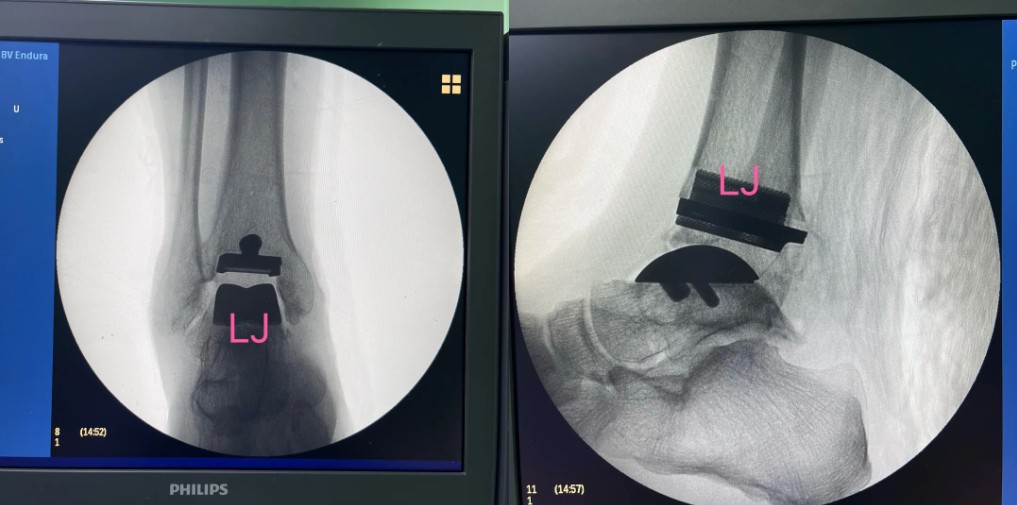

術(shù)后影像

3D打印個性化定制導(dǎo)板

3D打印定制化假體